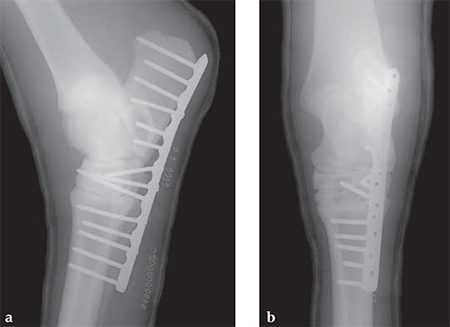

A 14-year-old Trakehner mare sustained a luxation of the proximal intertarsal joint (calcaneus and talus are displaced palmarly).

(Case provided by Alan Ruggles, Lexington Kentucky, USA)